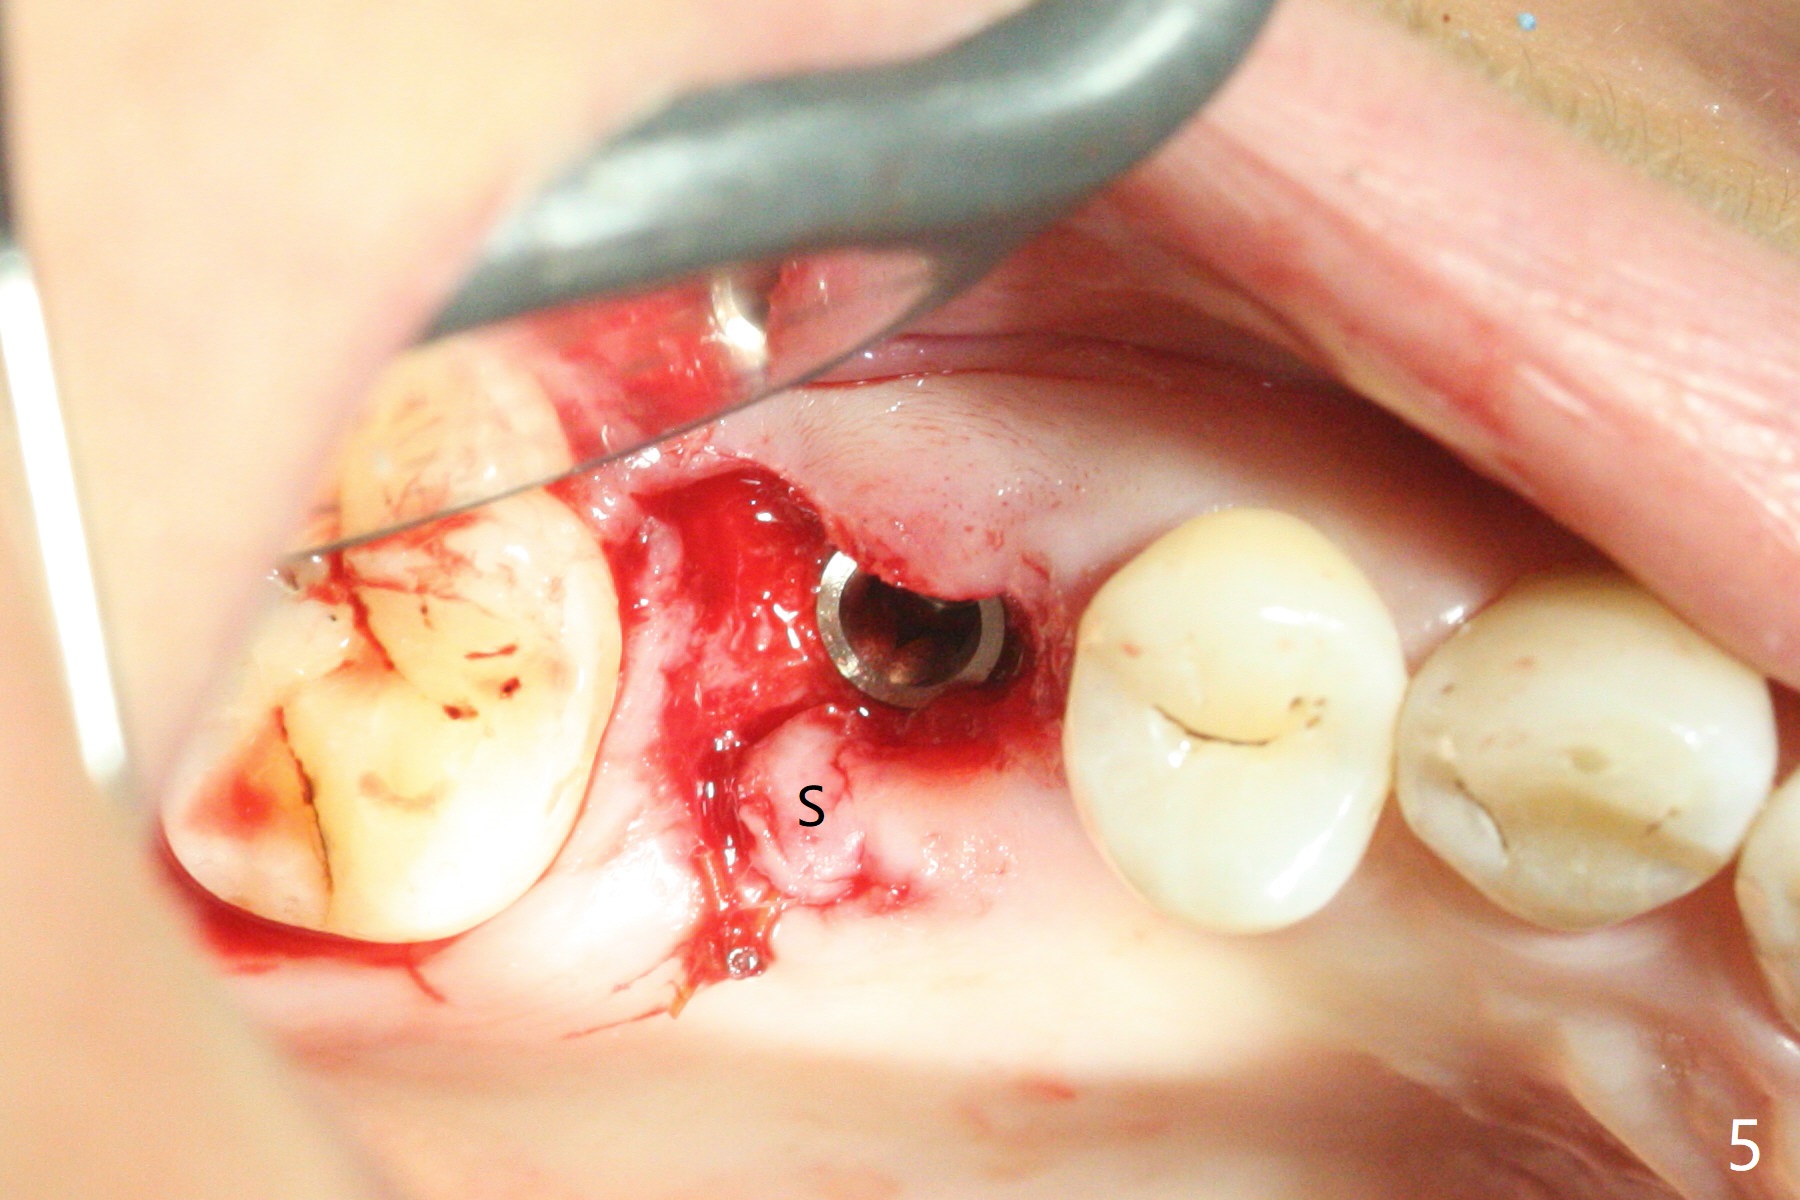

When the residual roots of the tooth #3 are removed, there is a gingival band over the septum (Fig.1 S). Osteotomy (Fig.2 yellow circle) would tear it off. To save the soft tissue, the buccal attachment is severed (Fig.3 black line), the flap is rotated palatal (Fig.3 curved arrow) and sutured in place (Fig.5 S). After sinus floor breakdown (use of sinus drill for 16 mm) and use of membrane lifter/water, two pieces of PRF membrane are inserted. The membrane is so slippery that it is easy to enter the sinus for further sinus membrane lift and later allograft placement (Fig.4 *). A 4.5x10 mm dummy implant is placed with high torque after 4x7.3 mm drill with 3 mm stopper so that 4.5x7.3 mm drill with 1 mm stopper is used before placement of a 5x8.5 mm final implant with ~ 35 Ncm (Fig.5-7). The patient reports anterior sinus wall tenderness with right nasal discharge a few days postop. The provisional has mobility without tenderness 1 week postop. It appears that the sinus membrane has been involved, which is quickly repaired probably by PRF. There is no pain when a 5.2x4(2) mm cemented abutment is torqued at 30-35 Ncm before impression (Fig.8). The surrounding soft tissue is healthy. When the permanent crown is delivered, the patient feels light pain when she bites hard. The discomfort persists 4 months post cementation (Fig.9). The crown/abutment is replaced with a healing abutment (Fig.10). There is no bone loss 4 months post healing abutment placement (14 months post implant placement, Fig.11). Upper Molar Immediate Implant, Prevent Molar Periimplantitis (Protocols, Table), Trajectory II, 31 Flap Not Transferred Xin Wei, DDS, PhD, MS 1st edition 07/26/2019, last revision 10/05/2020